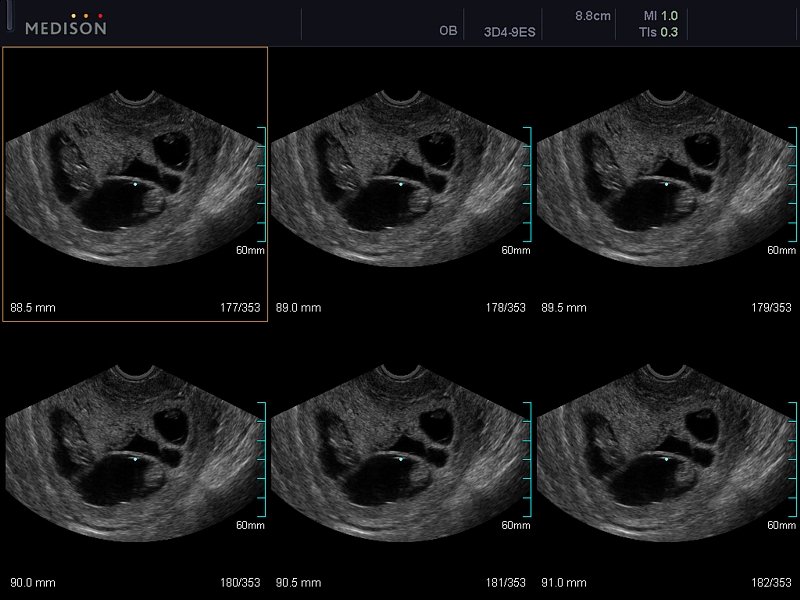

[EN] Эхограмма №606: Многоплодная беременность (двойня, ранние сроки) в режиме MSV (Multi-Slice View).

Изображение получено с помощью УЗ сканера Accuvix-V10 (снят с производства).